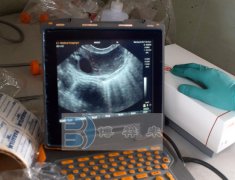

进口牛用B超仪诊断技术安全、无损伤,可以用来估计胎龄,监测胎儿生长,性别及诊断妊娠,观察生殖系统发育,进行疾病诊断等,建立奶牛胚胎和生殖系统变化的超声影像图集和变化

牛用B超诊断技术的用途很广泛,应用最多的是在动物生殖系统,迄今为止,还没有一种诊断仪器能像B超诊断仪那样受到畜牧工作者的青睐。在育种工作中具有重要利用价值,生产条件

牛活体采卵(OPU)是继体外受精(IVF)和胚胎移植(ET)之后的用于牛胚胎实验操作和生产繁殖的一项非常实用的胚胎工程技术。OPU技术克服了屠宰场取卵巢和体内超数排卵的缺点,而且这项技